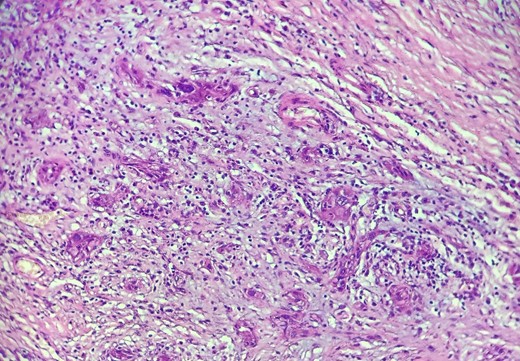

HE section: The tumor cells are so poorly differentiated that it is difficult to tell what the cell of origin is. The cells are discohesive with bizarre looking nuclei (×400).